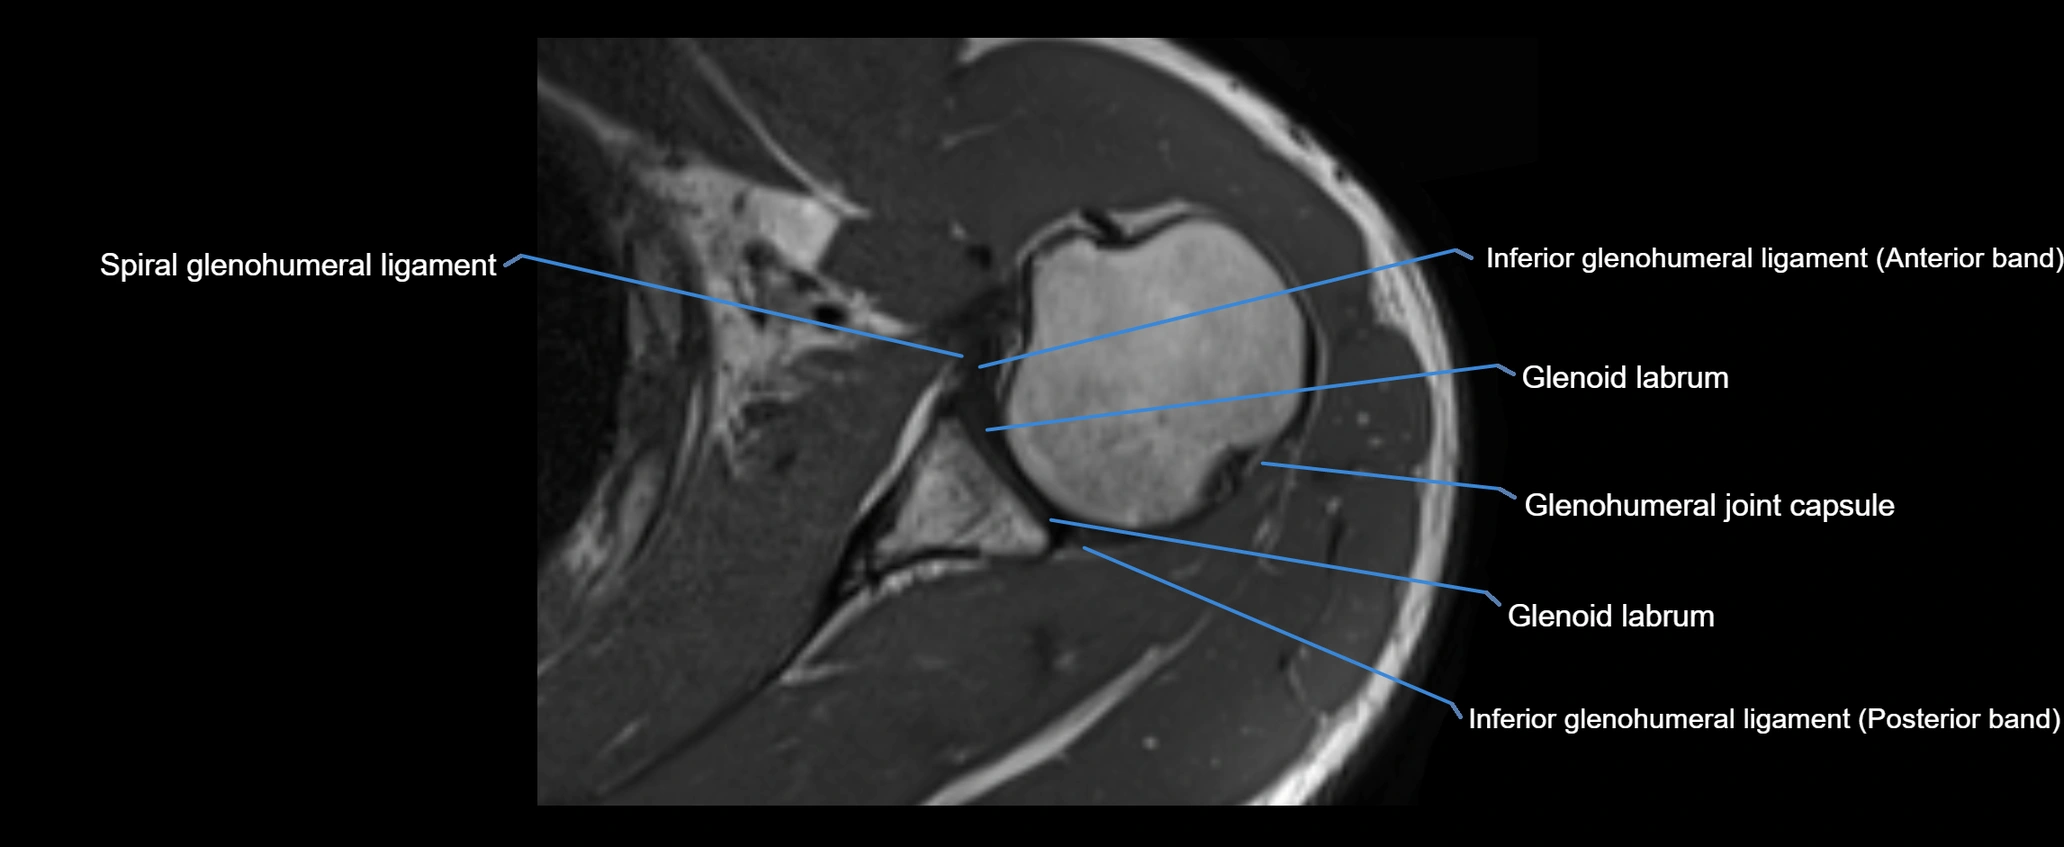

MRI Appearance

• T1-weighted images:

• Normal ligament: Low signal (dark linear band) spanning acromion to clavicle.

• Surrounding fat planes: Bright, delineating the ligament clearly.

• Marrow of clavicle and acromion: Bright due to fatty content.

• Tears: Discontinuity or irregular thickening with intermediate-to-bright signal.

• Chronic injury: Thinning, fraying, or irregular low-signal fibers with adjacent scarring.

• T2-weighted images:

• Normal ligament: Low signal, homogeneous.

• Partial tear or sprain: Focal hyperintensity or thickening.

• Complete tear: Discontinuity with fluid-bright gap between clavicle and acromion.

• Associated edema: Bright signal in distal clavicle or acromion marrow.

MRI images

image